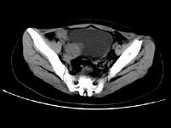

- 单项选择题女,24岁, 近日尿频明显,CT检查如图所示, 最可能的诊断是 ( )

A、膀胱癌

B、子宫肌瘤

C、卵巢癌

D、盆腔纤维瘤

E、卵巢囊肿